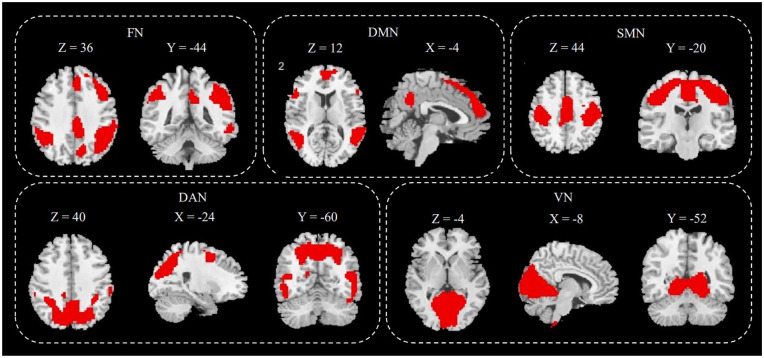

Methods: The study involved 23 chronic migraine, 37 episodic migraine, 21 trigeminal neuralgia patients, and 33 age- and gender-matched controls. Resting-state functional magnetic resonance imaging was performed, and five sets of brain network components were extracted through ICA. Neuronal activity indicators were calculated for each participant's independent components, including amplitudes of low-frequency fluctuation (ALFF) and regional homogeneity (ReHo). Functional connectivity was also assessed and compared among the four groups.

Results: Trigeminal neuralgia patients showed reduced ALFF in the dorsal attention network versus episodic migraine patients and controls. Both trigeminal neuralgia and chronic migraine patients had decreased ReHo in this network. Migraine patients had weaker connectivity between the default mode and visual networks than controls. Trigeminal neuralgia patients also showed higher connectivity between the somatosensory motor and dorsal attention networks. Compared to episodic migraine, trigeminal neuralgia, and chronic migraine patients had increased connectivity between the visual and dorsal attention networks.